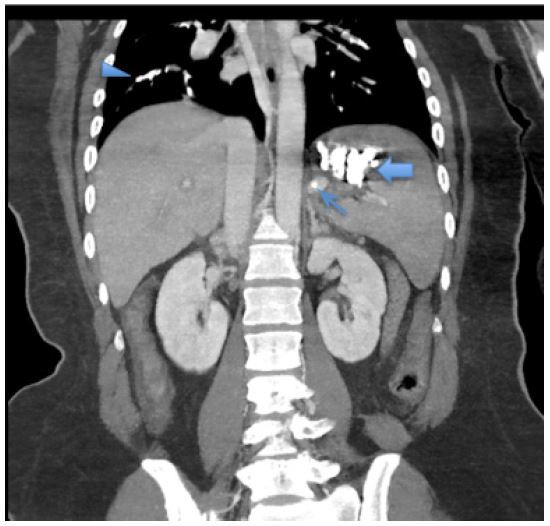

The patient received intravenous Sandostatin and proton pump inhibitors. Upper GI endoscopy revealed mild portal hypertensive gastropathy and a large gastric varix with red signs in the fundus, extending to involve esophageal varices (GOV 2), as per Sarin classification (Figure 1) [3]. Endoscopic sclerotherapy was performed with an injection of 1.5 ml N-Butyl-2-cyanoacrylate (Glubran®) diluted (50/50) with lipiodol into the fundic varix with red signs, under general balanced anesthesia. Airway management and intubation were uneventful. Injection sclerotherapy achieved successful hemostasis, maintaining stable hemodynamic and respiratory status throughout the procedure.

Figure 1: Retroversion view from an upper GI endoscopy showing a large gastric varix with red signs in the fundus.